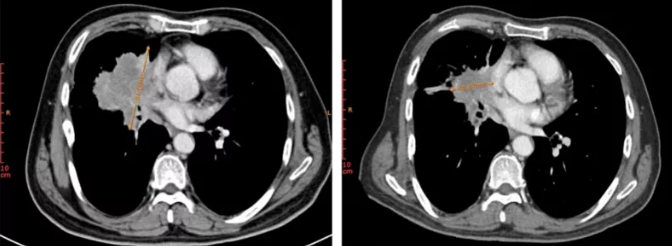

病例3患者为晚期肺鳞癌(包括EGFR、ALK、ROS1、BRAF V600E、MET外显子14、RET或NTRK基因组异常均为阴性),接受多西他赛+顺铂(DP)方案一线治疗,12个月后疾病进展。随后入组Ⅱ期临床试验接受MRG003治疗仅2次(6周),靶病灶直径总和缩小54.1%,疗效评估达PR(图3)。

图3. 治疗前(左)及治疗后(右)右肺门处病灶变化